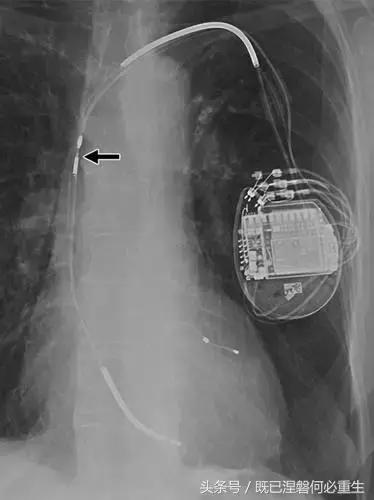

图。 6A 75岁的男性患有心房导线脱位。

A,Medtronic双腔起搏器的右心房导联(箭头)显示在正面(A)和外侧(B)图像上的纯垂直路线。 电极在心房中自由浮动。 患者抱怨经常心悸,并且设备检查显示不能可靠地去极化心房。 心房导线修订(未示出)导致心悸消除。 心房导线的推荐放置位于右心耳,但右心房中的导联可充分发挥作用。 在任一位置正确固定到壁上的引线通常将显示一定程度的曲率。